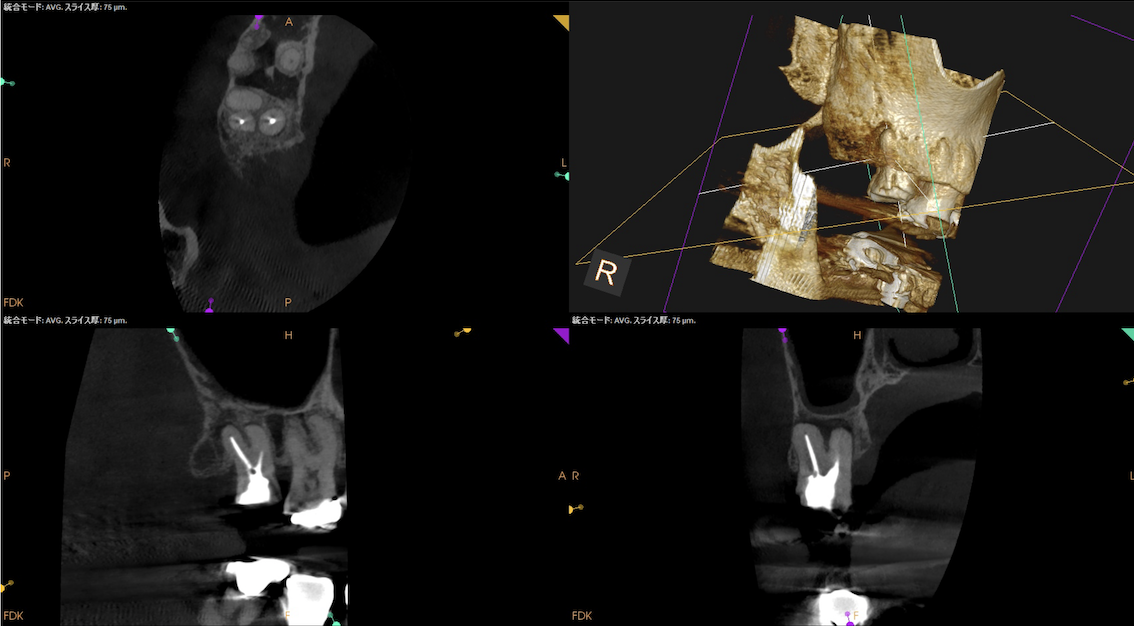

根尖病変があり頬側歯槽骨が穿孔しているDB, レンツロが破断しており根尖病変があるPをSelectiveに再根管治療するという方針を術前に決定した。

#2 Re-RCT(2026.3.9)

仮封を除去すると光る何かが目に入る。

レンツロはそこにあるようだ。

それの除去に没頭?すると時間を取られるのでまずはDBからだ。

が、根管口がどの辺りに存在するか?判然としない。

そこでMBのGutta Percha Pointを目印にDBを探索することにした。

SXで上部を拡大した後に根管形成した。

その後、Pだ。

レンツロは以下のようにして除去した。

全長8mmのレンツロは除去された。

まさに秒殺だ。

その後、以下のように形成した。

根管充填後にPA, CBCTを撮影した。

DB

P

問題はないだろう。